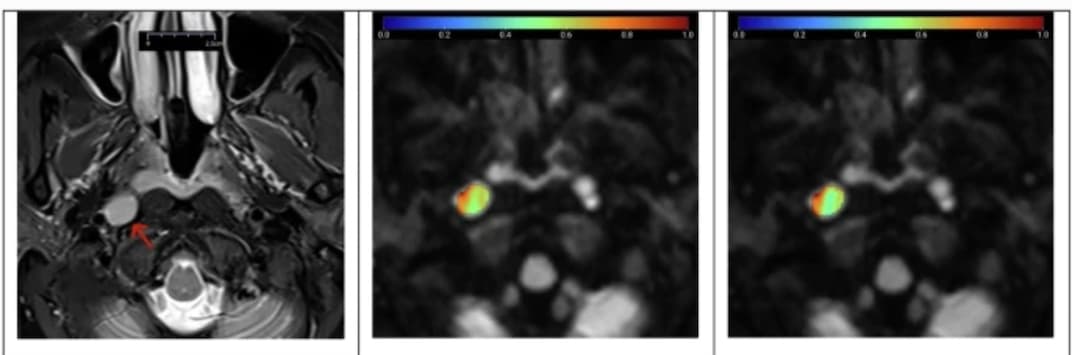

Distinguer les ganglions lymphatiques cervicaux bénins et métastatiques par IRM conventionnelle n’est pas facile. Une étude publiée dans la Revue European Radiology tente de différentier les ganglions lymphatiques bénins et métastatiques en combinant de nouveaux modèles d’IRM de diffusion et leurs caractéristiques morphologiques. Certains nouveaux modèles donnent des résultats convaincants.